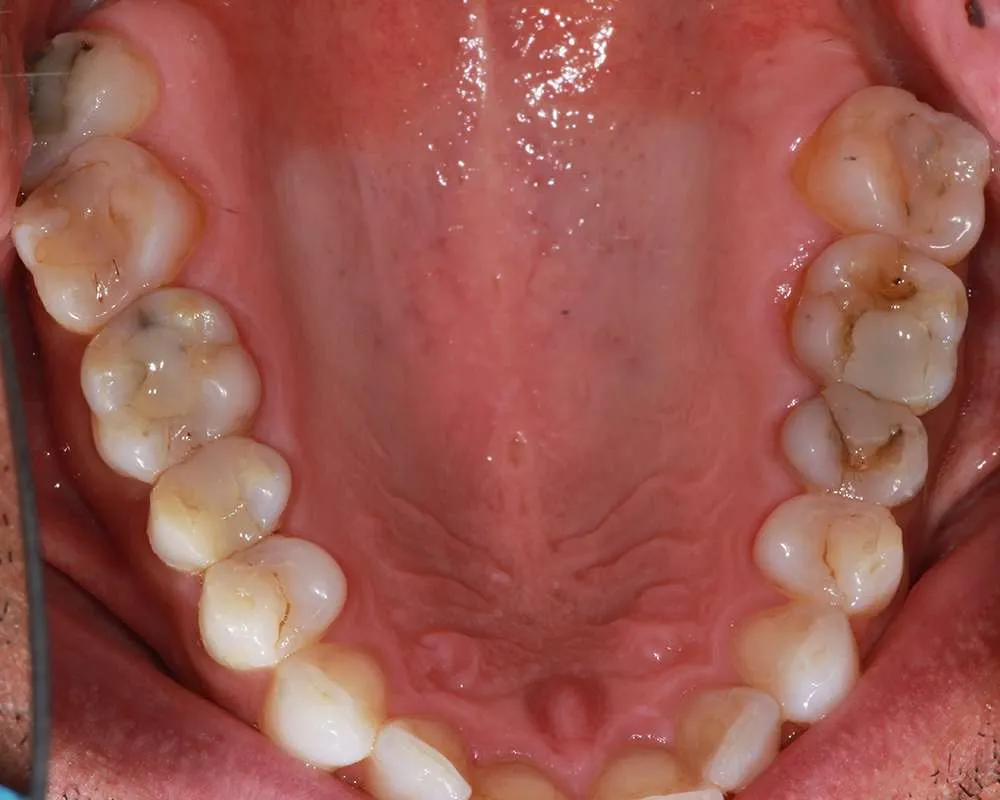

Real Stories, Real Results: Case Studies Showcasing How Our Personalized Approach Transforms Smiles and Lives

Complex Cases

Witness the Remarkable Changes We Can Achieve

The safe removal of mercury fillings is crucial for your health and well-being. At our practice, we follow strict protocols to ensure that mercury amalgam fillings are removed safely and effectively.